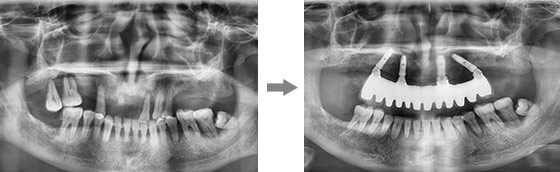

康贝佳胡主任为李大爷做了详细的口腔检查,并采用了ALL-ON-4技术,整个手术过程仅仅30分钟,只需4颗植体就恢复了半口牙,不仅创伤小、疼痛轻,恢复快,且为李大爷省了近一半的费用。

从术前诊断、手术种植、术后修复等一体化流程,通过口腔数字全景检查和CT片、牙槽骨条件测量、三维模拟种植、血常规检查,制定个性化专属种牙方案,根据缺牙老人的时间、费用、年纪多方面综合考虑,做到让缺牙老人放心种牙,满意种牙。